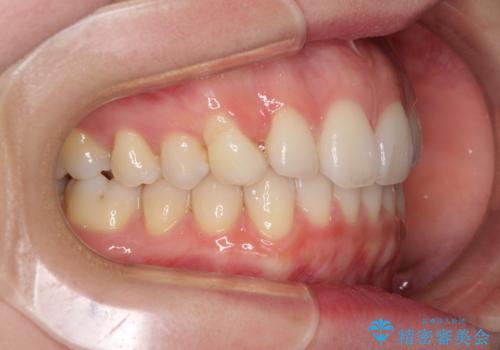

- 前歯のクロスバイトや残存している乳歯を気にして来院された患者様です。

上顎骨の幅が下顎骨よりも小さいので、拡大装置により骨幅を広げて上下関係を改善し、その後インビザラインにて歯並びを整えることとしました。

上下の骨幅を改善したことで、スムーズに歯列矯正を行うことができました。